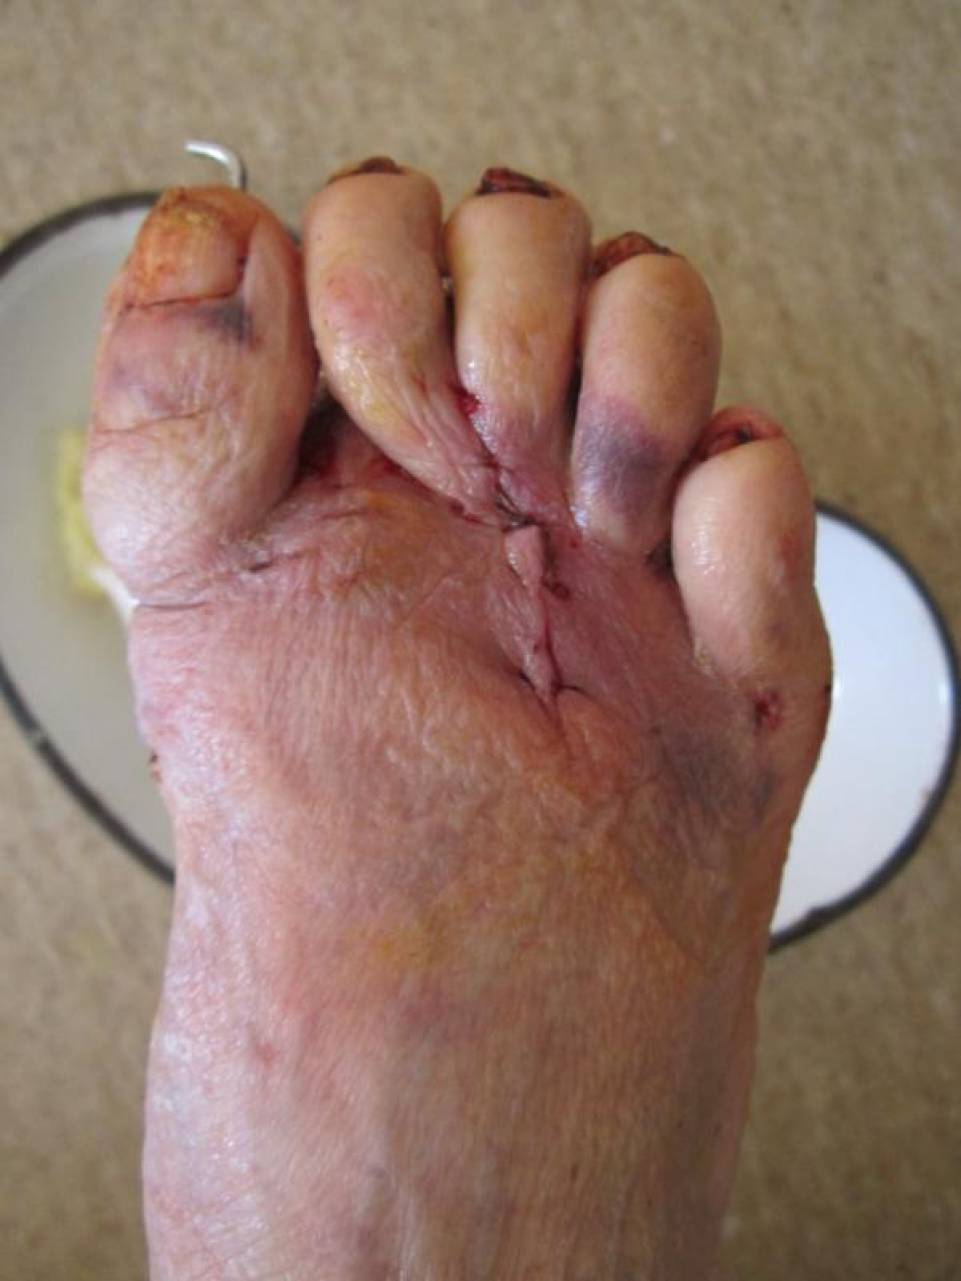

Пациентке выполнен артродез 1-ого плюснефалангового сустава, резекции

говок 2-3 плюсневых костей, субкапитальная остеотомия 4 плюсневой кости,

тенотомиии разгибаталей 2-5 п. стопы. Раны зажили первичным натяжением.